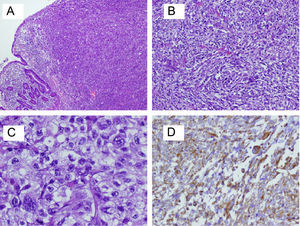

Para el estudio anatomopatológico, se recibió una pieza de 230mm de longitud, que presentaba una tumoración circunferencial de 50×30mm, parcialmente ulcerada, que infiltraba 10mm la pared, dando lugar a estenosis marcada de la luz. En el examen microscópico, se observó una tumoración constituida por una proliferación bifásica de células fusiformes y células epiteliodes, con marcada atipia, numerosas mitosis y áreas de necrosis, que se disponían formando haces que se entrecruzaban (fig. 4A–C). La tumoración invadía toda la pared muscular del intestino llegando a la grasa subserosa. Los márgenes quirúrgicos estaban libres de tumor. Se aislaron 18 ganglios del mesenterio sin que se observara metástasis en ninguno de ellos. El diagnóstico emitido fue de carcinoma sarcomatoide pobremente diferenciado, con invasión de subserosa.

En el estudio inmunohistoquímico, se observó positividad para marcadores propios de los tumores epiteliales, como la citoqueratina AE1-AE3 o antígeno epitelial de membrana (EMA), así como positividad en las mismas células, para marcadores propios de las células sarcomatosas, como la vimentina (fig. 4D). A su vez, las células tumorales mostraban pérdida de marcadores propios de las células intestinales, como la citoqueratina 20, debido a un proceso de indiferenciación. Otros marcadores, como actina músculo liso, desmina, CD117, CD34, fueron negativos, lo cual descartaba otros sarcomas, como tumores del estroma gastrointestinal y leiomiosarcoma.

Desde el punto de vista microscópico, el carcinoma sarcomatoide se caracteriza por la coexistencia de 2 componentes celulares malignos: uno predominante de células epiteliales carcinomatosas, cúbicas o columnares de núcleo hipercromático, y otro de células mesenquimales fusiformes, pleomórficas, de disposición sarcomatosa (con núcleo ovalado, nucléolo prominente, citoplasma eosinofílico, y frecuente actividad mitótica), que además, se puede acompañar de un componente con diferenciación rabdomioblástica, osteoblástica, cartilaginosa, grasa o neuroblástica.

En el estudio inmunohistoquímico puede apreciarse positividad para diversos marcadores, entre ellos citoqueratinas, antígeno carcinoembrionario (CEA), EMA, propios de la célula epitelial, y vimentina, propio de la célula mesenquimal7,11.